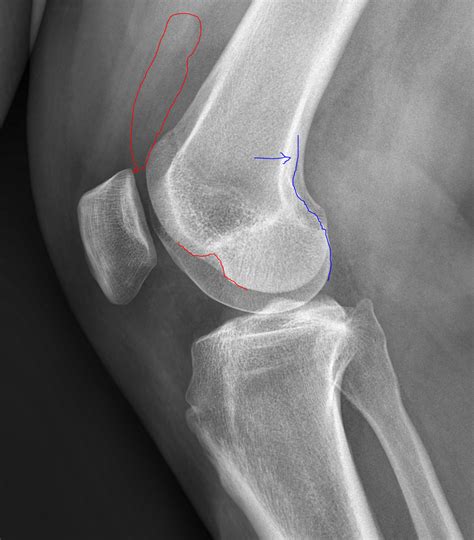

Learn how to interpret a lateral knee X-ray with our expert guide. We cover essential diagnostic views, anatomy identification, and common findings like joint effusions or fractures. Improve your radiographic assessment skills and clinical accuracy when evaluating knee pain, bone abnormalities, and joint health through high-quality imaging analysis and standard orthopaedic positioning techniques.

Read full article: Lateral Knee Xray